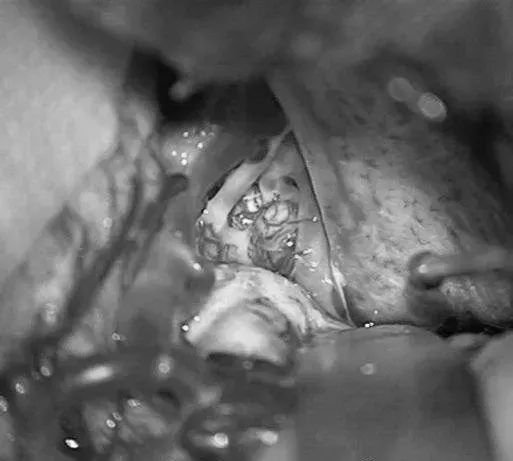

▼右侧眶颧开颅,经侧裂入路,牵开颞极暴露来自ICA鞍上段、MCA的M1段、PCA的P2段和小脑幕切迹。

▼电凝供应颞叶内侧面型AVM的PCA的P2供血支,减少畸形团血供。

▼移除AVM

▼显露PCA周围至其ParOccA和CalcA(P2P)分叉

▼沿小脑幕见PCA的大脑脚段(P2A)和硬化的供血支。